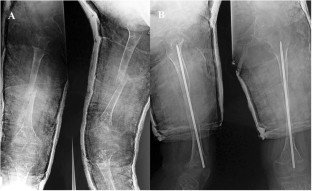

Fig. 1